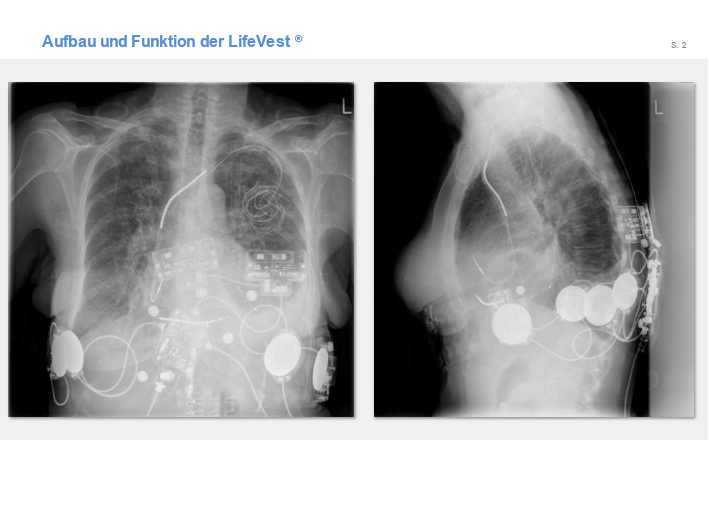

LifeVest

Folien